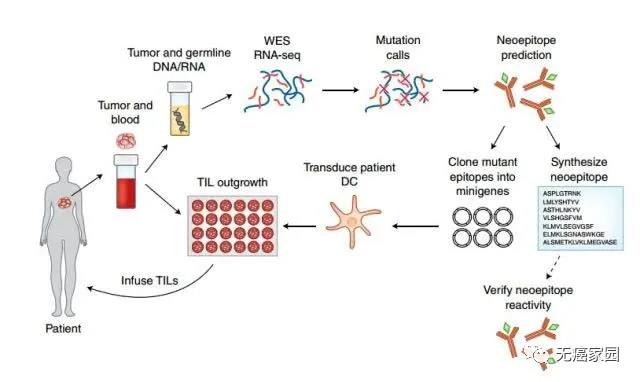

其实,TILs疗法尤其独特之处,与一般的细胞免疫疗法有很大的差别,被认为是为患者“量身定制”。

免疫细胞来源不同

TIL的免疫细胞来自于肿瘤组织,而其他细胞免疫疗法大部分来取自血液。这直接决定了免疫细胞识别肿瘤的能力。据估计,肿瘤里分离出的免疫细胞,有60%以上能识别肿瘤,而血液里面分离的免疫细胞,不到0.5%。

利用突变精准识别癌细胞

这种新型的疗法不是简单的扩增回输,而是要确定患者病例中特定的突变,之后利用突变信息找到能够最有效瞄准这些突变的T细胞,最后提取出专门患者肿瘤中细胞突变的T细胞,这些细胞具有精准识别癌细胞的能力。

TILs新疗法独特的制备方式

(1)得到患者的肿瘤组织块,其中混杂着体积较大的肿瘤细胞以及体积小而圆的T淋巴细胞;

(2)将不同种类的T淋巴细胞在细胞板上克隆化,并加入高浓度的IL-2来选择培养;

(3)在IL-2的刺激下不同种类的T淋巴细胞都得到了克隆扩增,形成了细胞群;

(4)用患者的肿瘤细胞和扩增后的T淋巴细胞反应,凡是能够发生杀瘤效应的T淋巴细胞群作为阳性TIL群留下(红色),其余的丢弃;

(5)用负载了肿瘤特异性抗原的树突状细胞(DC)进一步扩增培养肿瘤特异性的TIL;最后,回输给预先做了清髓的肿瘤患者。